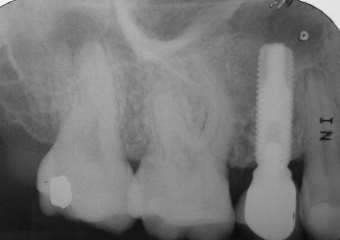

Raio X inicial

Raio X com Implante Instalado